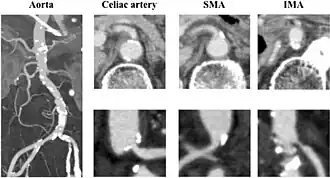

| CT angiogram demonstrating stenosis of the superior mesenteric artery. | |

Abdominal angina is diagnosed by identifying stenosis with imaging.[10] Since the symptoms of abdominal angina overlap with various other disorders, other causes of symptoms are ruled out as a part of the diagnostic process. Gastric ulcers, abdominal aortic aneurysms, and gastrointestinal cancers can have similar symptoms and can be ruled out by esophagogastroduodenoscopy, CT scans, or MR angiogram. Other differential diagnoses include GERD, dietary or food sensitivities, constipation, pancreatitis, abdominal abscess, appendicitis, irritable bowel syndrome, gastroenteritis, hepatitis, and inflammation of the gastrointestinal system.[11] Duplex ultrasound, MR angiography, angiography, and computed tomography angiography can be used to help confirm the diagnosis of abdominal angina.[3] Duplex ultrasound may be used to screen for abdominal angina but is not ideal for visualizing stenosis. Angiography, MR angiography, or CT angiography can be used to further visualize the celiac and mesenteric arteries.[12]